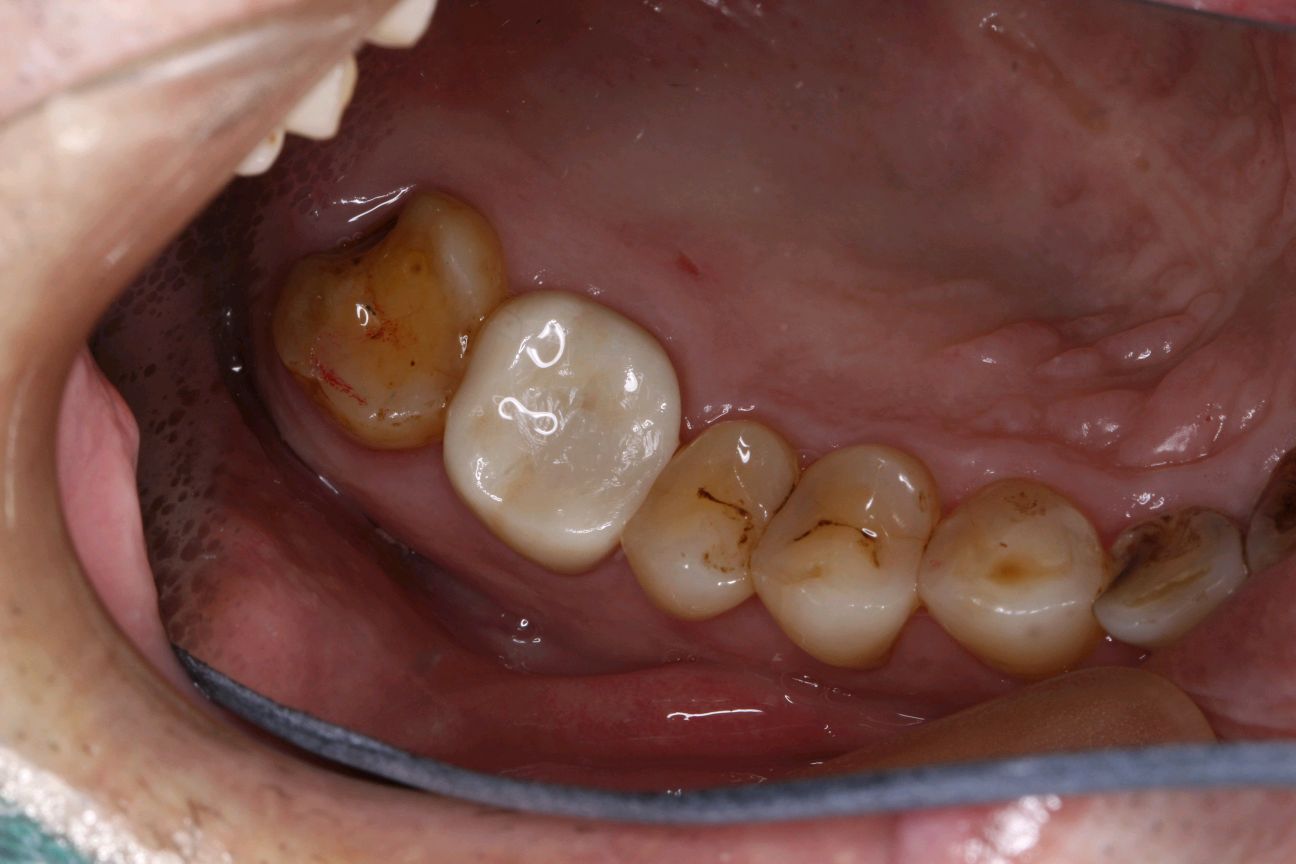

后牙重度磨损、能够维持咬合垂直距离,患者有足够的后牙支持,修复后可以建立稳定的正中颌位关系,上、下颌牙均可以磨出适当间隙容纳修复材料时----可以对磨损的牙齿进行全冠修复。

术后照片